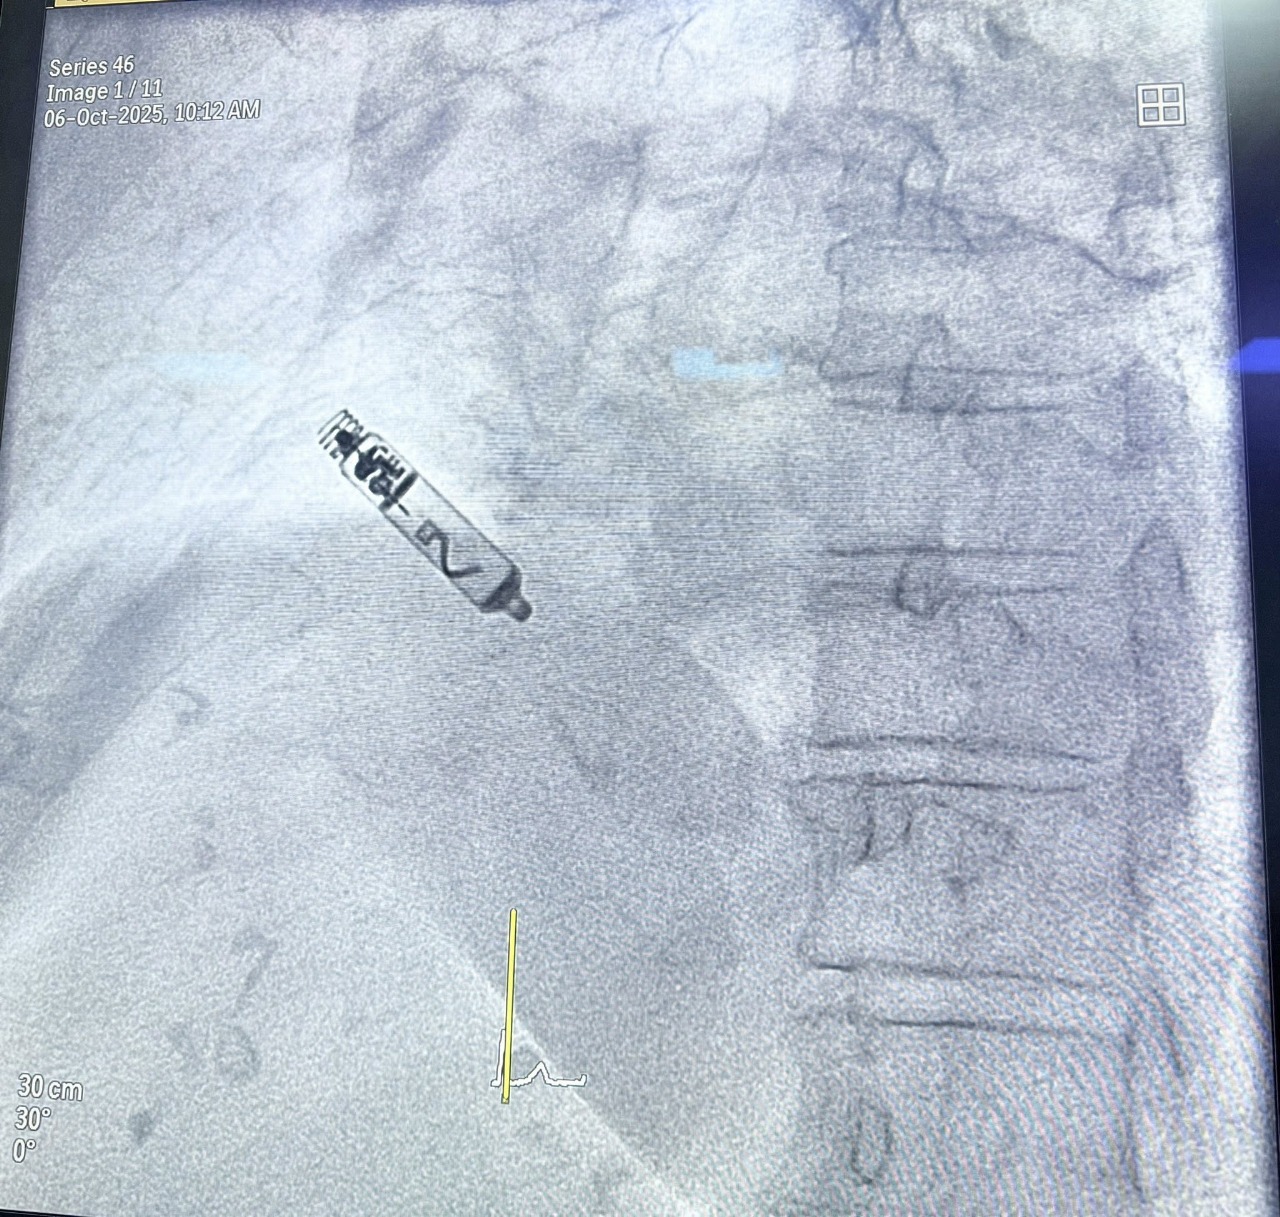

New Delhi: A 66-year-old woman has become the first patient in India to receive a leadless atrial pacemaker, following a minimally invasive procedure performed at Indraprastha Apollo Hospital in New Delhi.

Offering an alternative, Dr Vanita Arora, Clinical Lead for Cardiac Electrophysiology at Indraprastha Apollo Hospital, proposed the use of an Atrial Aveir Leadless Pacemaker—a capsule-sized, wireless device that can be implanted transcatheter into the right upper chamber of the heart, without the need for open surgery.

Successfully performed India’s first Atrial Aveir Leadless Pacemaker implant in a 66-year-old patient.